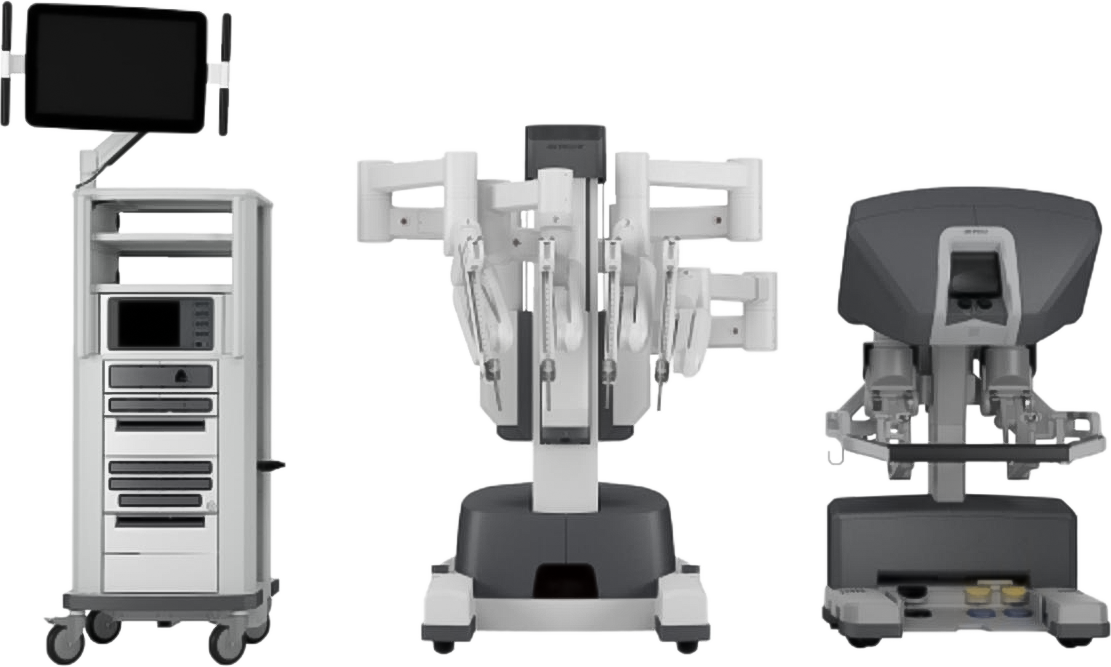

ロボット心臓手術

2421 症例

※2005年12月-2026年5月出血量

1cmほどのキーホール(鍵穴)を3カ所開け、ロボットアーム(鉗子)や内視鏡カメラを挿入して手術を行います。3D内視鏡カメラにより、術野を鮮明な3D映像で患部を拡大視野で捉えることができ、ロボットの鉗子をミリ単位の操作してオペを遂行します。

“ダビンチ”キーホール手術は、手術支援ロボット“ダビンチ(da Vinci Surgical System)”を用いたロボット手術です。開胸することなく、骨を切らず、数カ所のキーホールからすべての操作が遂行できるので、術中の出血が少なく、術後の痛みも軽く、また大きな傷が残らないため美容的にも優れています。従来のように人工心肺などを使用して遂行していた手術が“ダビンチ(da Vinci Surgical System)”の出現により劇的に変化し、術後経過や術中の体への負担が軽減できるようになりました。“ダビンチ(da Vinci Surgical System)”のような内視鏡手術の進歩は心臓だけでなく、すべての領域で目覚ましい発展を遂げています。現在では珍しいものでは無く標準の手術方法として認められる傾向にあり、新たなアプローチとして広い分野で採用されています。

手術支援ロボット“ダビンチ(da Vinci Surgical System)”を用いた手術が行われるようになり、これまでよりも心臓疾患手術の術式の幅が広がったため、多くの症例へのアプローチが可能になりました。当院では2022年8月に1000例の手術実績があります。心臓疾患をお持ちの患者様へ迅速に手術へと踏み切ることが可能になったことで、完治へと導いた件数が飛躍的に増加しました。診療実績とその経過が手術の精度を実証していることでしょう。

そして、手術における傷を1cm程度にし、患者様が早期に社会復帰ができるよう支援するロボット手術は多くの領域で採用が進んでいます。例えば甲状腺疾患などでも、「傷を小さく」「首ではなくわきの下から患部にアプローチ」することが可能になり、患者様の身体への負担を大きく減らすことができるようになりました。特に傷が残ることへの不安を覚えやすい女性の方にとっては大きな変革と言えるでしょう。このように従来の問題を克服し、より良い治療を実現できるのが、ロボット手術の魅力の一つだと言えます。

※体力の消耗減や傷口の小ささなど、体に対する負担を軽減すること

完全内視鏡下外科手術で「切開しない治療」を実現

手術支援ロボット“ダビンチ”を使用したロボット手術は、骨を切らずに小さな傷口のみでオペを行い、出血量・痛みの減少を実現します。早期の社会復帰が可能な手術です。

骨を切ることなく数カ所の

キーホールからすべての操作を

da Vinci Surgical System